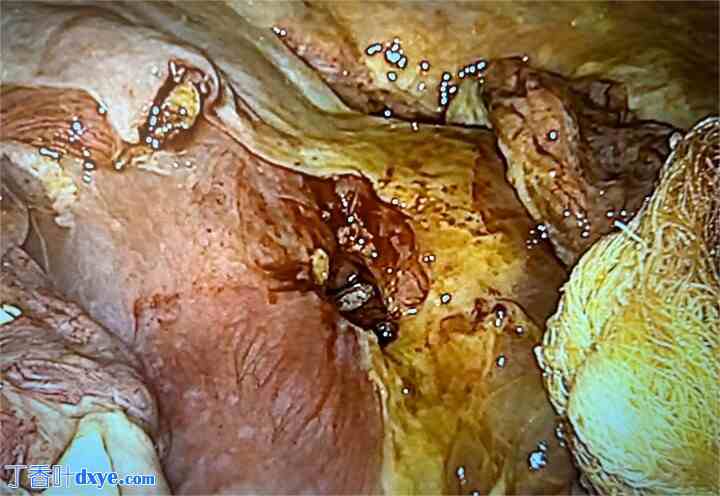

探查性腹腔镜检查发现大量肠液、纤维素性渗出物、肠袢水肿,以及胃空肠吻合口处1厘米的溃疡(图1)。清创后,使用可吸收聚己内酯缝线,采用连续缝合技术封闭缺损。缝合处加固使用大网膜片(图2和图3)。对腹腔进行抽吸和冲洗。患者术后无并发症出院。术后6个月的内镜检查显示溃疡持续存在(图4)。

清创后的溃疡边缘

图 3.

缺损处采用可吸收缝线缝合。